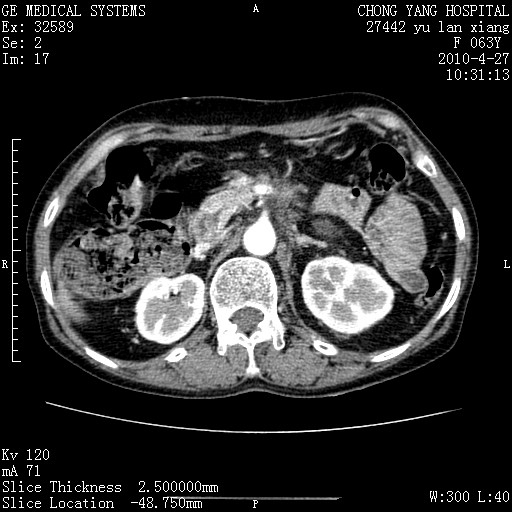

标题: CT26066:F63Y 上腹正中压痛半月,CA199:7400u/ml,MR示胰腺炎伴 [打印本页]

胰腺癌侵犯腹腔动脉干-分支、胃壁、左侧膈肌伴胰周及腹膜后淋巴结转移、胆囊切除术后。

胰腺癌侵犯腹腔动脉干-分支、胃壁、左侧膈肌伴胰周及腹膜后淋巴结转移、胆囊未显影。